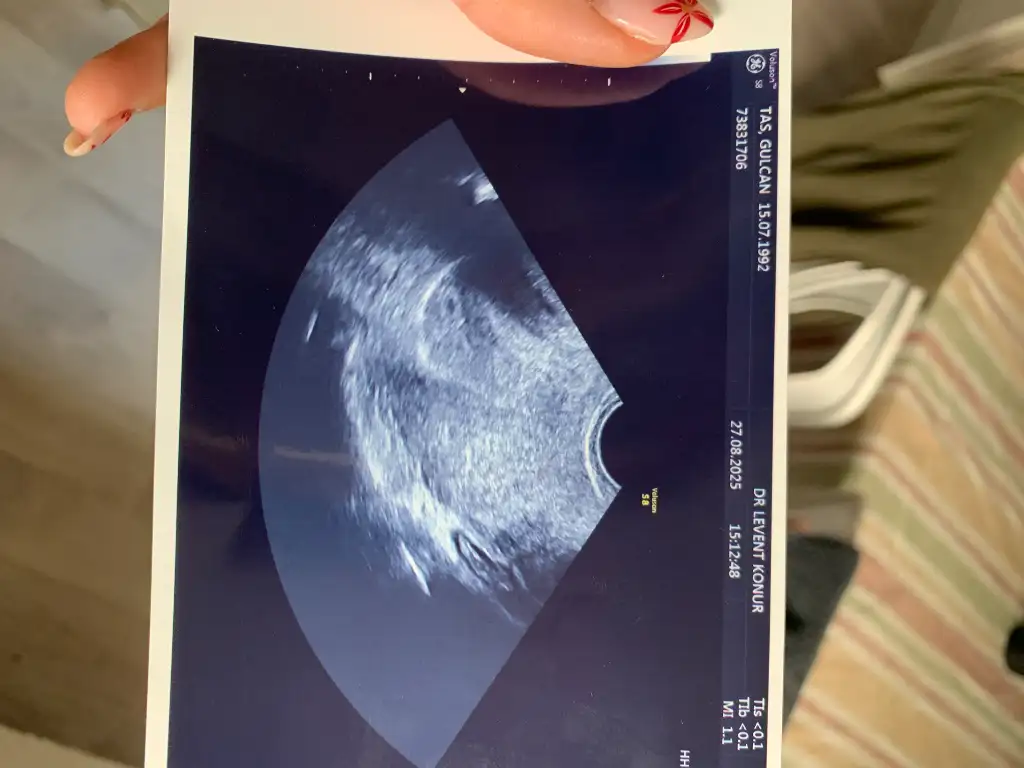

5+2 deyiz bugün devlette bi görünmek istedim eski doktoruma genelde takibimi devlet hastanesinde yaptırdım miyomlarım olduğu için

10mm erken gebelik kesesi dedi embriyo yolk sac değerlendirilmedi daha erken 2hafta sonra gel bakalım dedi

cuma günü özeldeki doktorumda kontrolüm var 5+4 te acaba birşey görür müyüz çok endişeliyim korkuyorum gerginim :((